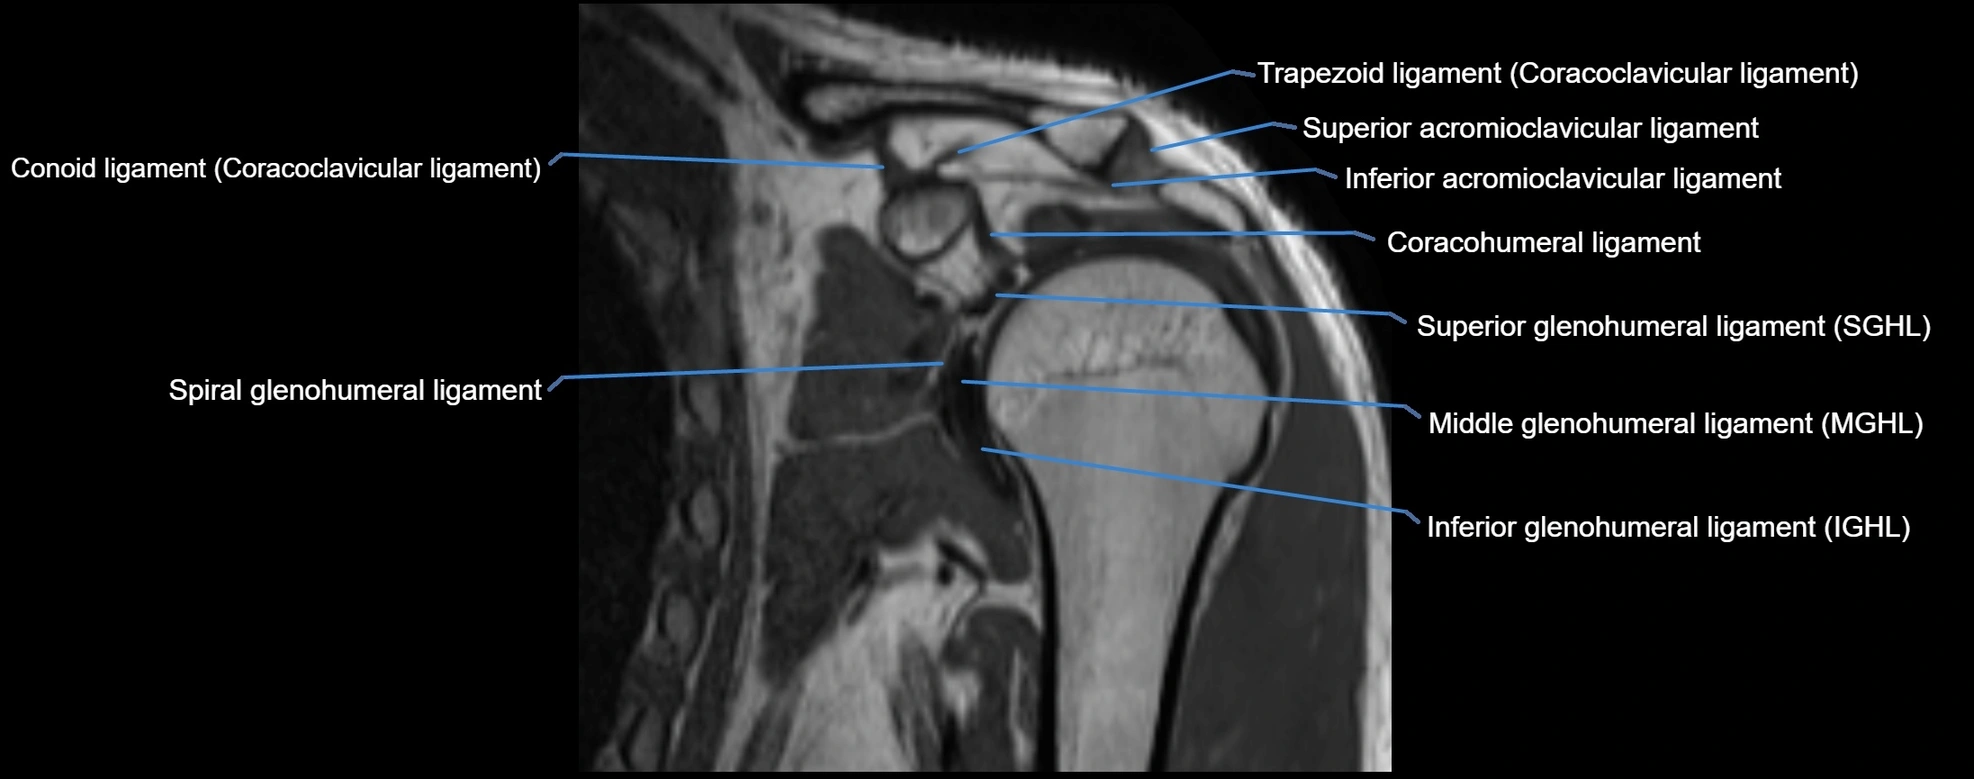

MRI images

image